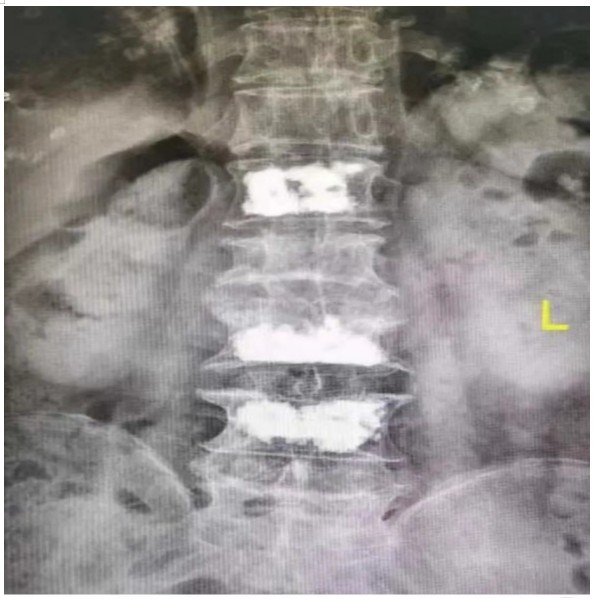

原來,89歲的占大爺因在家勞作時(shí)突發(fā)腰背部疼痛難忍、腰部無法直立,行走困難,在家臥床休息兩周后疼痛仍未減輕,于是來到衡陽市中心醫(yī)院脊柱外科就診。接診的盛凱醫(yī)師仔細(xì)查體結(jié)合磁共振檢查發(fā)現(xiàn),占大爺腰椎L1、L3、L4有椎體壓縮骨折,診斷為腰椎體壓縮骨折、重度骨質(zhì)疏松癥。錢軍博士團(tuán)隊(duì)結(jié)合對病人多椎體的骨折做出了細(xì)致的評估,經(jīng)過認(rèn)真分析研究,決定為患者實(shí)施腰椎體壓縮性骨折經(jīng)皮穿刺椎體成形術(shù)(PVP)。手術(shù)當(dāng)天,醫(yī)師團(tuán)隊(duì)在C-臂監(jiān)視器透視下,分別定位L1、L3、L4雙側(cè)椎弓根位置,以標(biāo)記穿刺點(diǎn)為中心做3mm切開,在透視下注入骨水泥,再次透視見骨水泥位置良好,順利完成手術(shù)。

據(jù)悉,該手術(shù)經(jīng)皮透視下穿刺,手術(shù)切口小,創(chuàng)傷小,無需縫合,微創(chuàng)手術(shù)皮膚切口僅2-3毫米,僅僅一個(gè)穿刺針的長度,通過穿刺針注入骨水泥,骨水泥可以達(dá)到穩(wěn)定椎體骨折、恢復(fù)椎體力學(xué)強(qiáng)度、防止椎體進(jìn)一步壓縮和緩解疼痛的目標(biāo),使患者早期恢復(fù)正?;顒?dòng)。優(yōu)點(diǎn)為創(chuàng)傷小,臥床時(shí)間短,花費(fèi)少。對于老年人椎體骨折微創(chuàng)下椎體成形術(shù)為最適宜該患者的治療方法。術(shù)后患者即感腰部疼痛明顯減輕,第二天可下床行走,已無腰痛不適,如此快速地恢復(fù)讓患者占大爺非常高興,自己再也不會受腰痛折磨整日與床為伴了,當(dāng)即給脊柱外科團(tuán)隊(duì)送上了錦旗表示感謝。